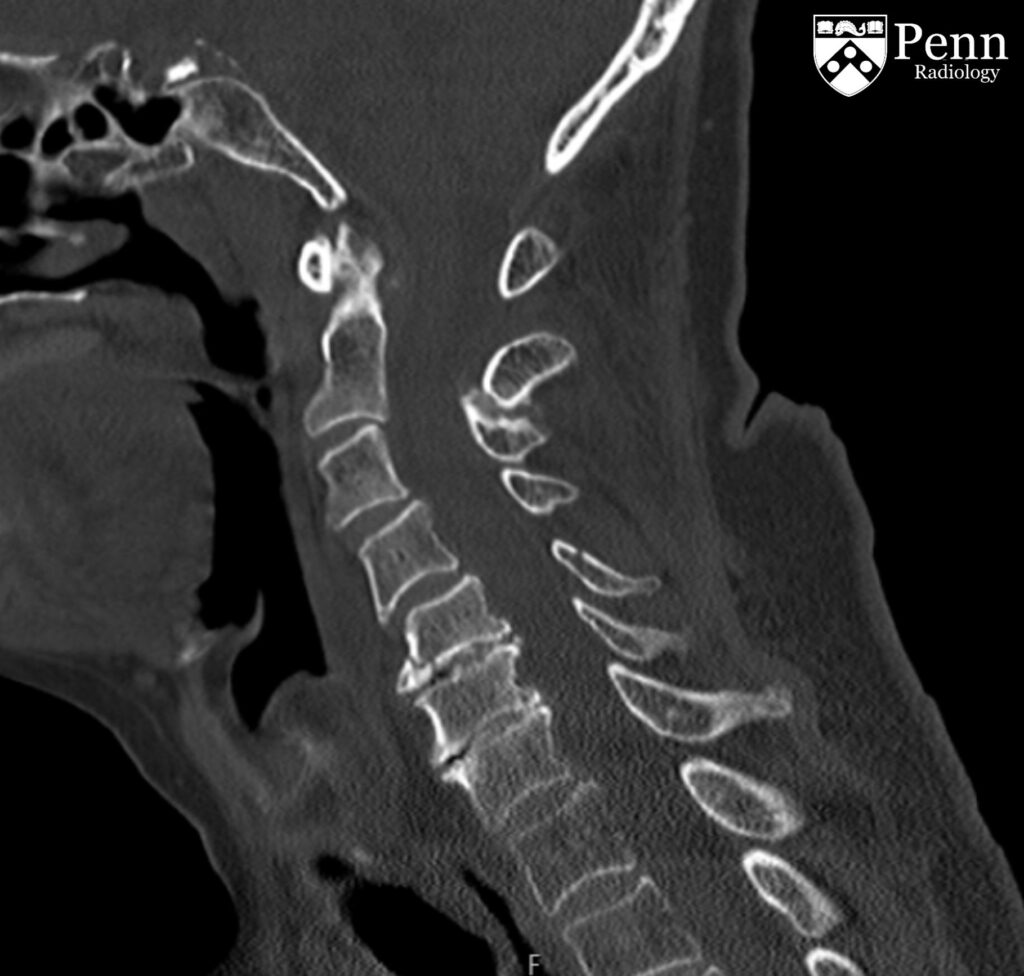

33-year-old woman after motor vehicle collision

A 33-year-old woman status post motor vehicle collision.